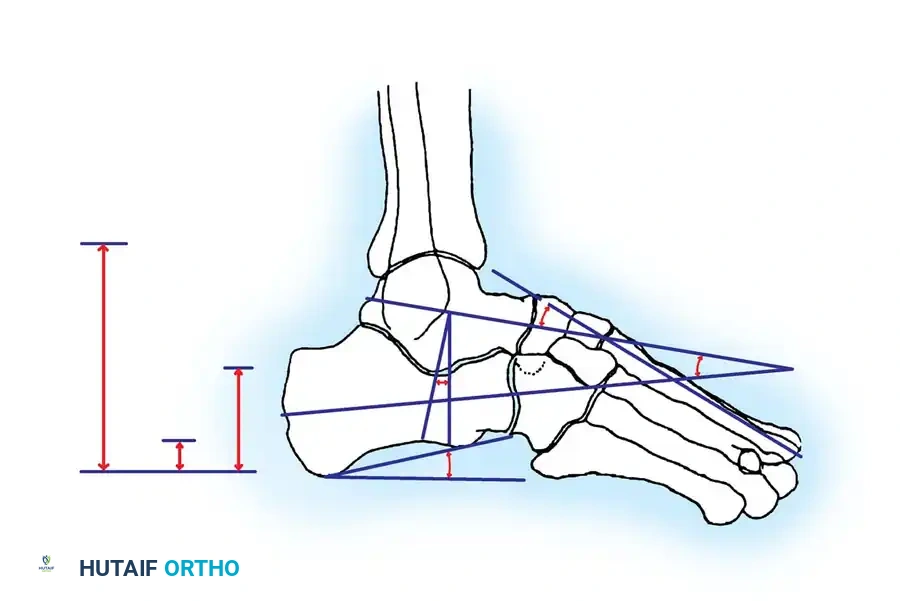

Böhler's Angle

The Böhler angle is formed by the intersection of two lines on the lateral radiograph: one drawn from the highest point of the anterior process to the highest point of the posterior facet, and another from the highest point of the posterior facet to the highest point of the calcaneal tuberosity.

A normal Böhler angle ranges from 25° to 40°. In intraarticular fractures, this angle is typically flattened or reversed, indicating severe collapse of the posterior facet and loss of calcaneal height.

The Brodén View

The Brodén view is critical for visualizing the posterior facet. It is obtained by internally rotating the leg 40 degrees with the ankle in neutral dorsiflexion. The x-ray beam is then angled cephalad at 10, 20, 30, and 40 degrees to visualize different portions of the facet from posterior to anterior.

- Lateral View: Assesses the loss of calcaneal height, rotation of the posterior facet, and the Böhler angle.

- Axial (Harris) View: Evaluates the varus/valgus alignment of the tuberosity, heel widening, and lateral wall blowout.

- Anteroposterior (AP) View: Assesses calcaneocuboid joint involvement.

- Oblique View: Highlights the anterior process and the calcaneocuboid articulation.

- Brodén View: Used intraoperatively and postoperatively to evaluate the congruency of the posterior facet.